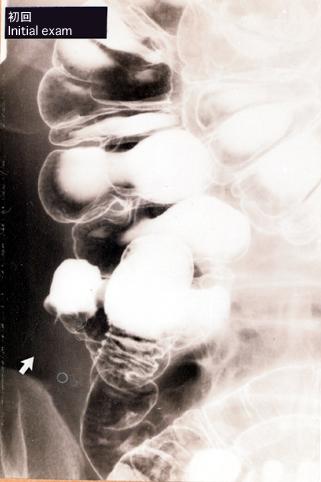

症例提示(所在地,施設名等): 東京都・ 国立がんセンター中央病院と九州がんセンターの共同作成

症例登録日 2003/10/09

画像数 10

性別 男性

年齢 40-44

画像ID:5952

疾患(病理主体)の分類炎症性・潰瘍性疾患/その他

部位(臓器別)大腸/虫垂

検査方法X-P